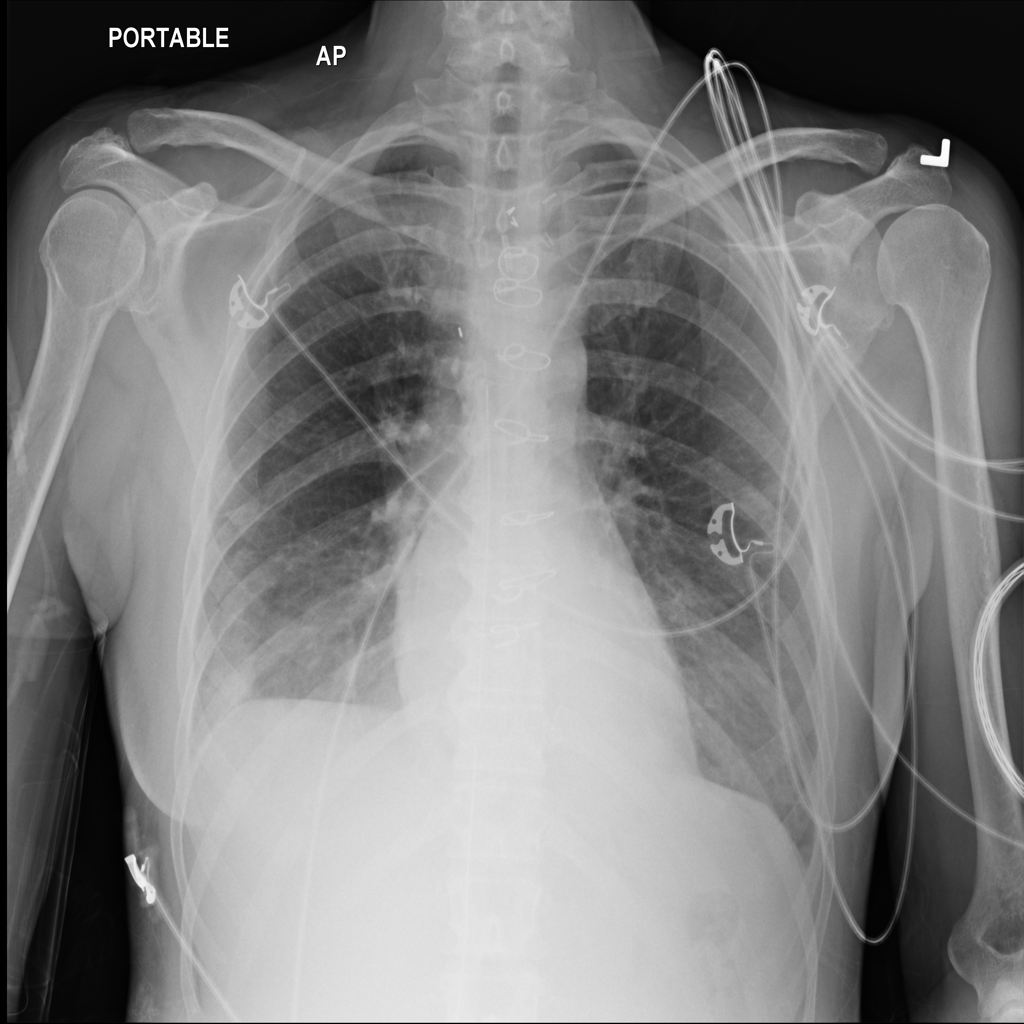

Pleural Effusion

Pleural effusion means extra fluid has collected around the lung in the pleural space. It can happen with heart problems, infection, inflammation, or other underlying conditions.

Showing up to 90 reference images for Effusion.

PAT-86C8 · IMG-000Effusion

PAT-86C8 · IMG-000

PA